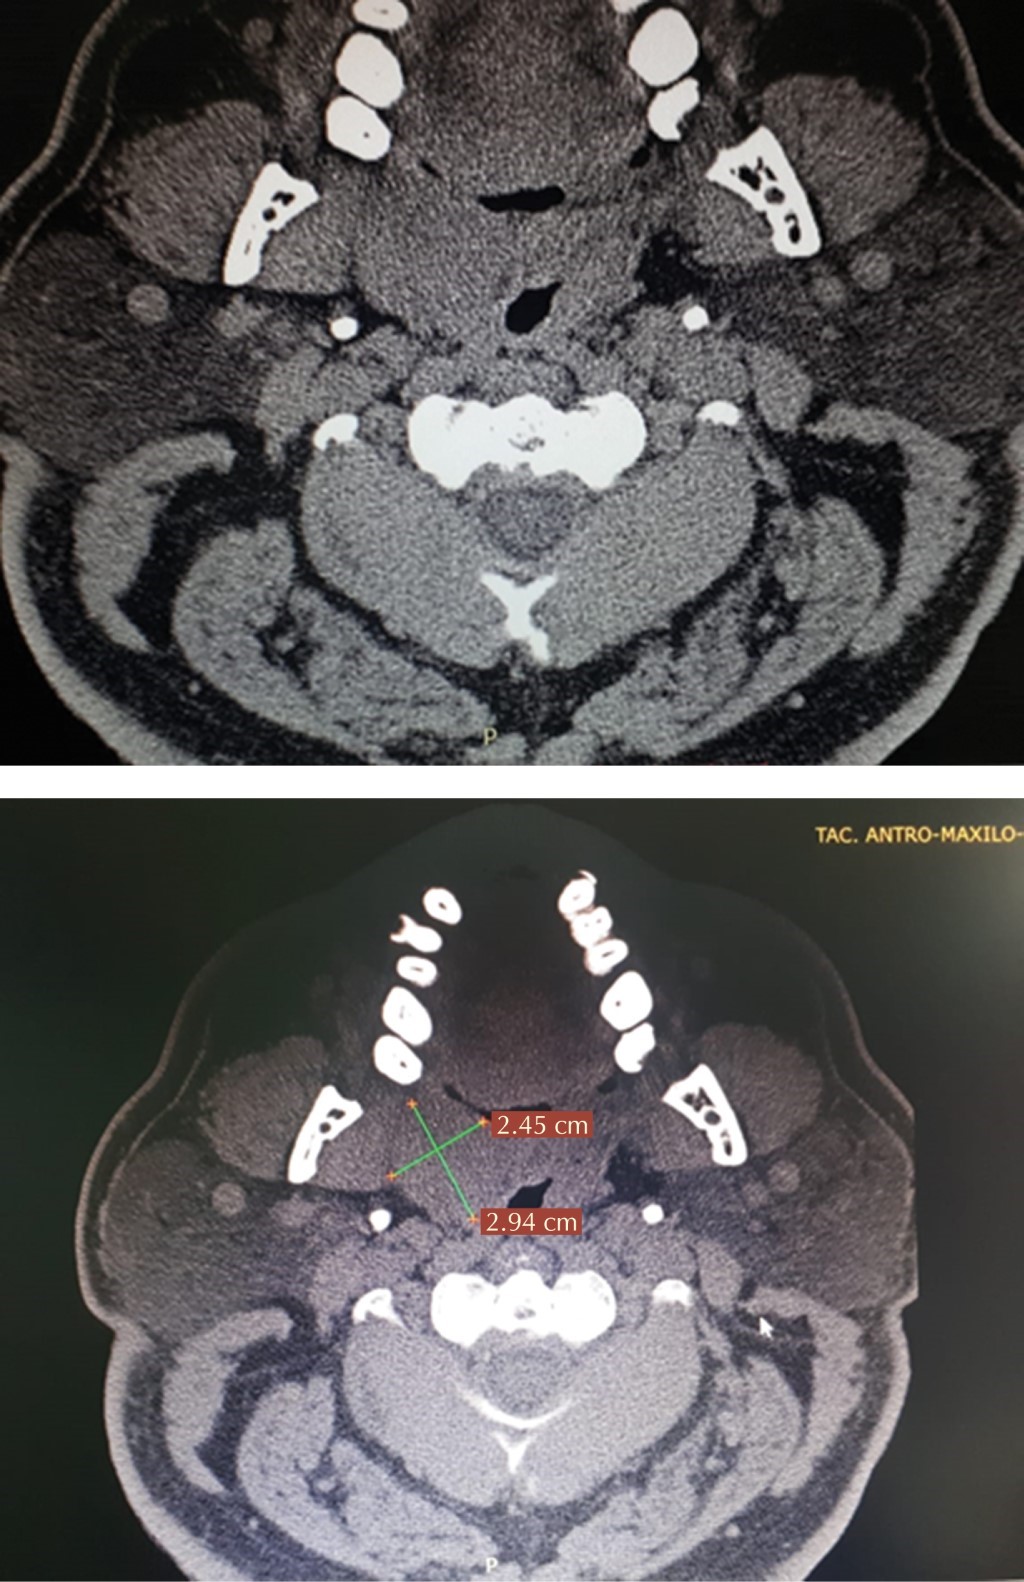

En la tomografía se aprecia tumoración palatina con una dimensión de 2 × 3 × 2 cm, hipodensa y homogénea, de bordes no nítidos, desplazando ligeramente vía aérea hacia el lado izquierdo, no apreciando refuerzo de medio de contraste (Figuras 2 y 3).

Figura 2

Figura 3